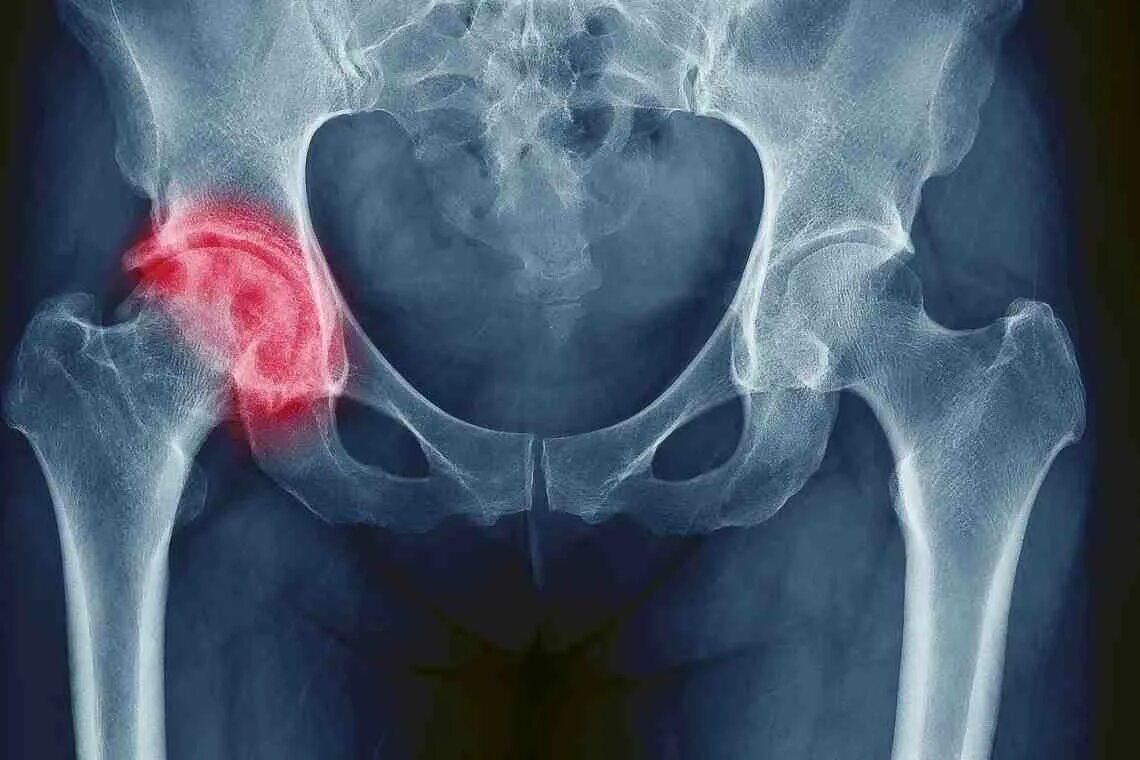

Артрит тазобедренного сустава симптомы